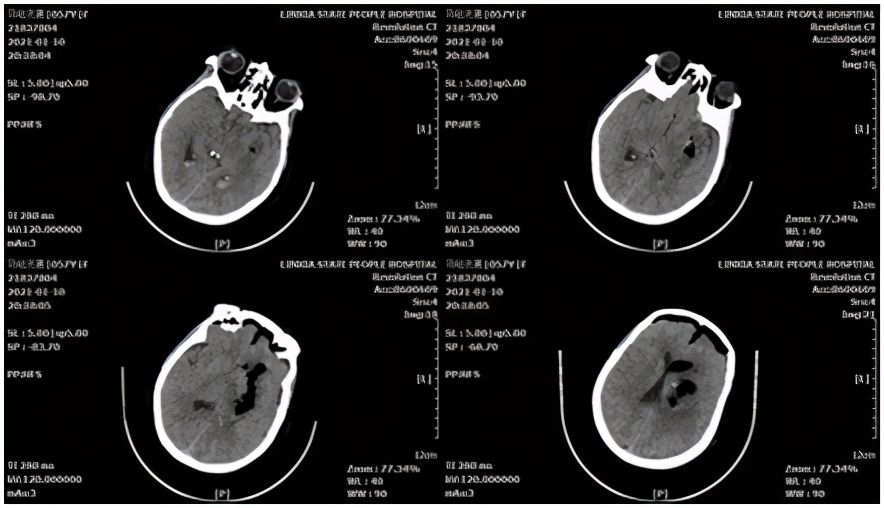

小脑出血病例,患者男性,77岁。主因"突发意识障碍,恶心、呕吐4小时",于2021-02-02,急诊以"高血压脑出血"收入院。头颅CT示:右侧小脑出血破入第四脑室,梗阻性脑积水形成。

术前头颅CT

术中采用 幕下 旁正中入路,并用血肿-脑脊液置换技术,最终清除小脑半球、第四脑室全部血肿,术后血肿腔不放置引流管,取得了良好效果。

术后头颅CT